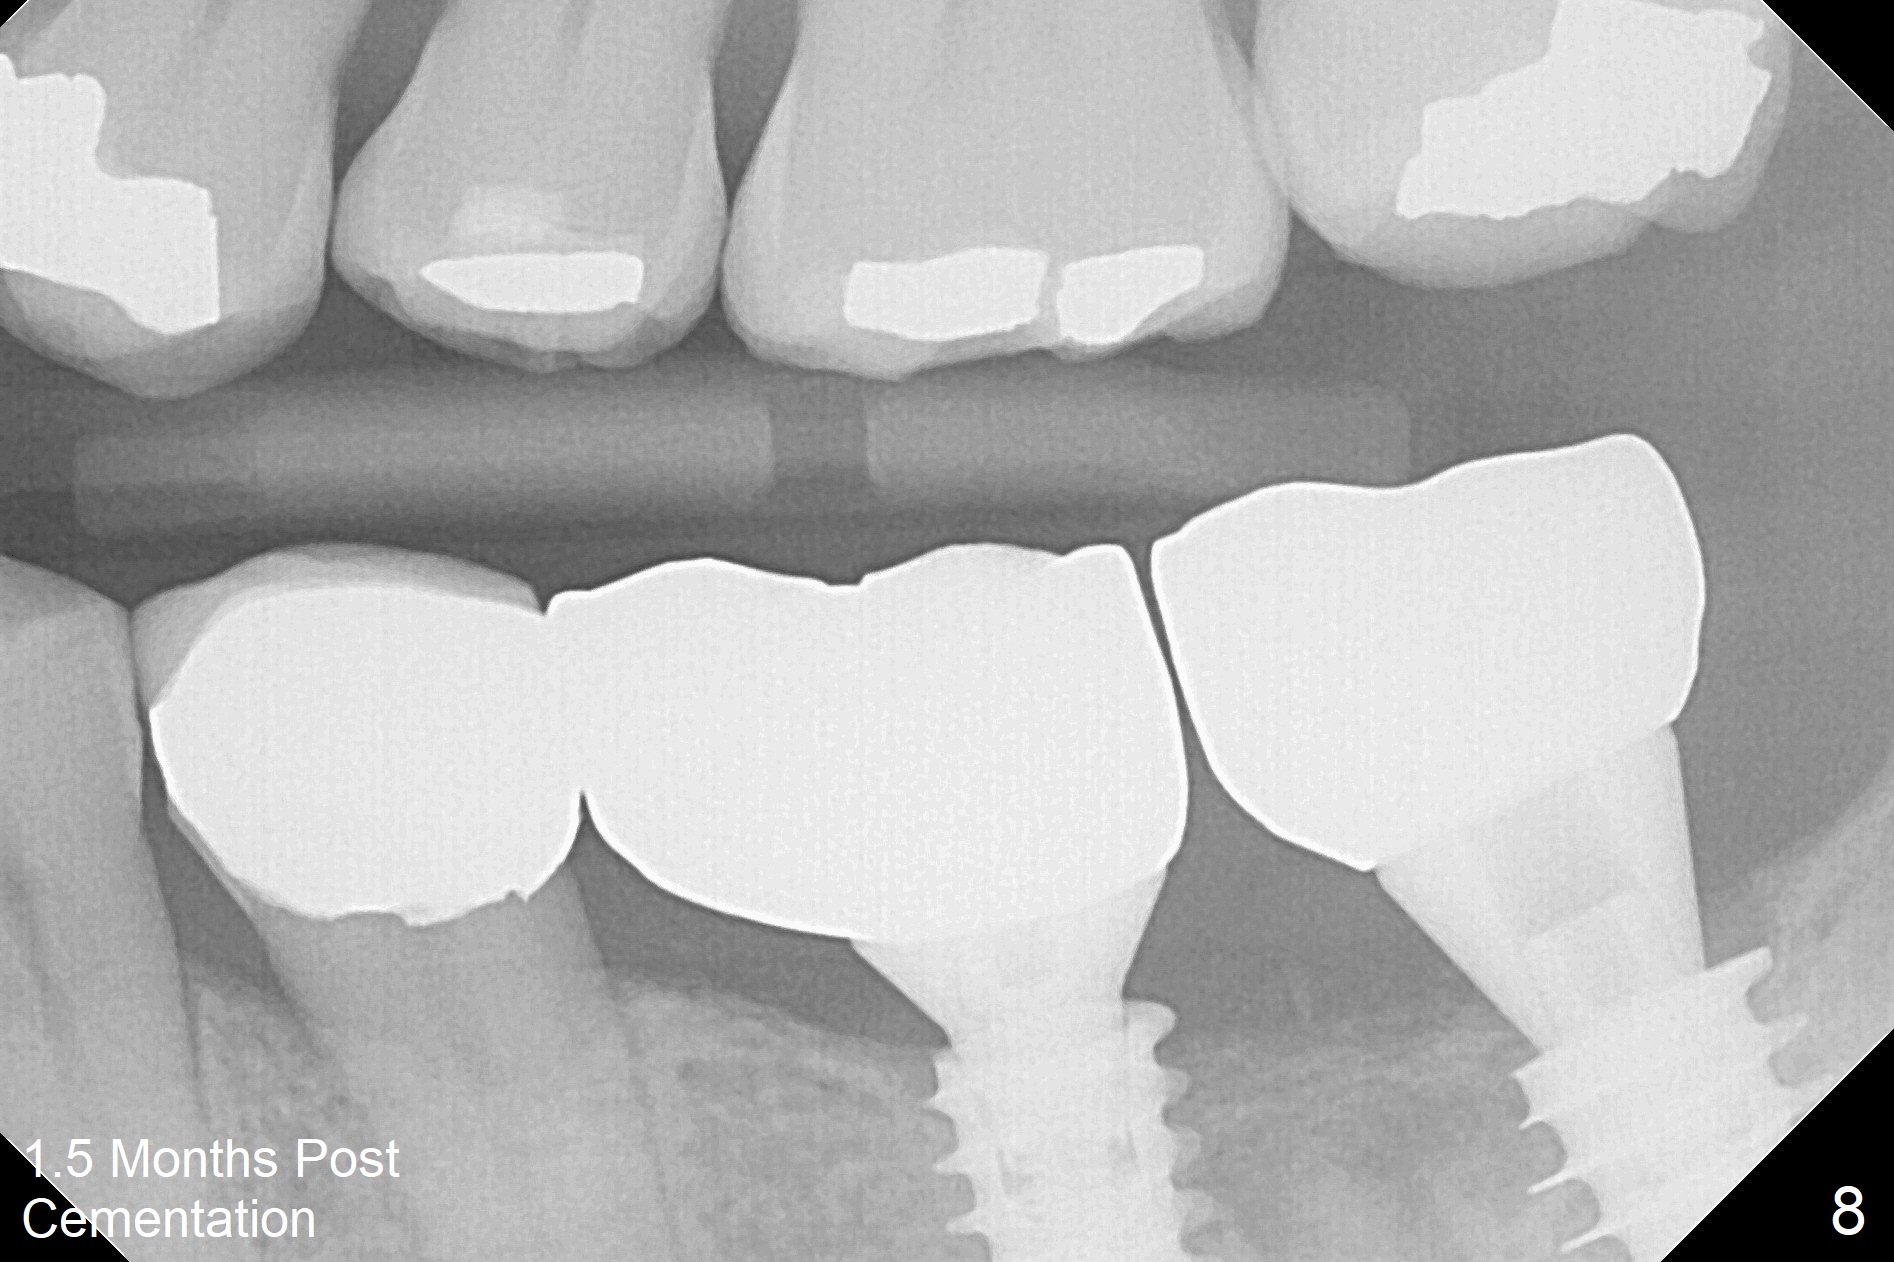

A drawback of placing an implant in the distal socket of the 2nd lower molar is closer to the Inferior Alveolar Canal. The implants seem to have osteointegrated 4.5 months postop (Fig.5). While the ridge at #19 appears to be wider than preop (as compared to Fig.1), that at #18 seems to be atrophic 5 months postop (Fig.6 * (1 week post cementation)). The distal implant placement at #19 may increase possibility of abutment screw loosening during functioning (Fig.7 *). When the patient returns for periodic exam 1.5 months post cementation, loose contact between the implant crowns is noted (Fig.8). The bony trabeculae form between the 2 implants crestally 12 months postop, i.e., 7 months post cementation (Fig.9). The loose contact between the 2 implants is corrected 14 months post cementation.